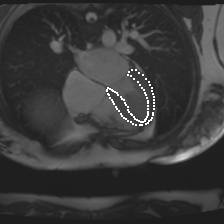

Accurate segmentation and motion estimation of myocardium have always been important in clinic field, which essentially contribute to the downstream diagnosis. However, existing methods cannot always guarantee the shape integrity for myocardium segmentation. In addition, motion estimation requires point correspondence on the myocardium region across different frames. In this paper, we propose a novel end-to-end deep statistic shape model to focus on myocardium segmentation with both shape integrity and boundary correspondence preserving. Specifically, myocardium shapes are represented by a fixed number of points, whose variations are extracted by Principal Component Analysis (PCA). Deep neural network is used to predict the transformation parameters (both affine and deformation), which are then used to warp the mean point cloud to the image domain. Furthermore, a differentiable rendering layer is introduced to incorporate mask supervision into the framework to learn more accurate point clouds. In this way, the proposed method is able to consistently produce anatomically reasonable segmentation mask without post processing. Additionally, the predicted point cloud guarantees boundary correspondence for sequential images, which contributes to the downstream tasks, such as the motion estimation of myocardium. We conduct several experiments to demonstrate the effectiveness of the proposed method on several benchmark datasets.